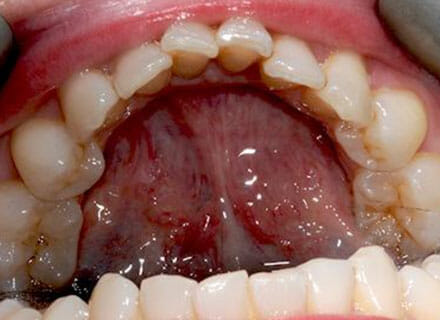

In this case, we needed to reduce the size of the central incisors as they were just too big. This combined with the crowding at the front had caused the lateral incisors to become trapped inside, pushing the big central incisor teeth forwards even more. After reducing the big teeth to a normal size we started with fixed clear bracket brace treatment and were able to complete this case in a little over a year.